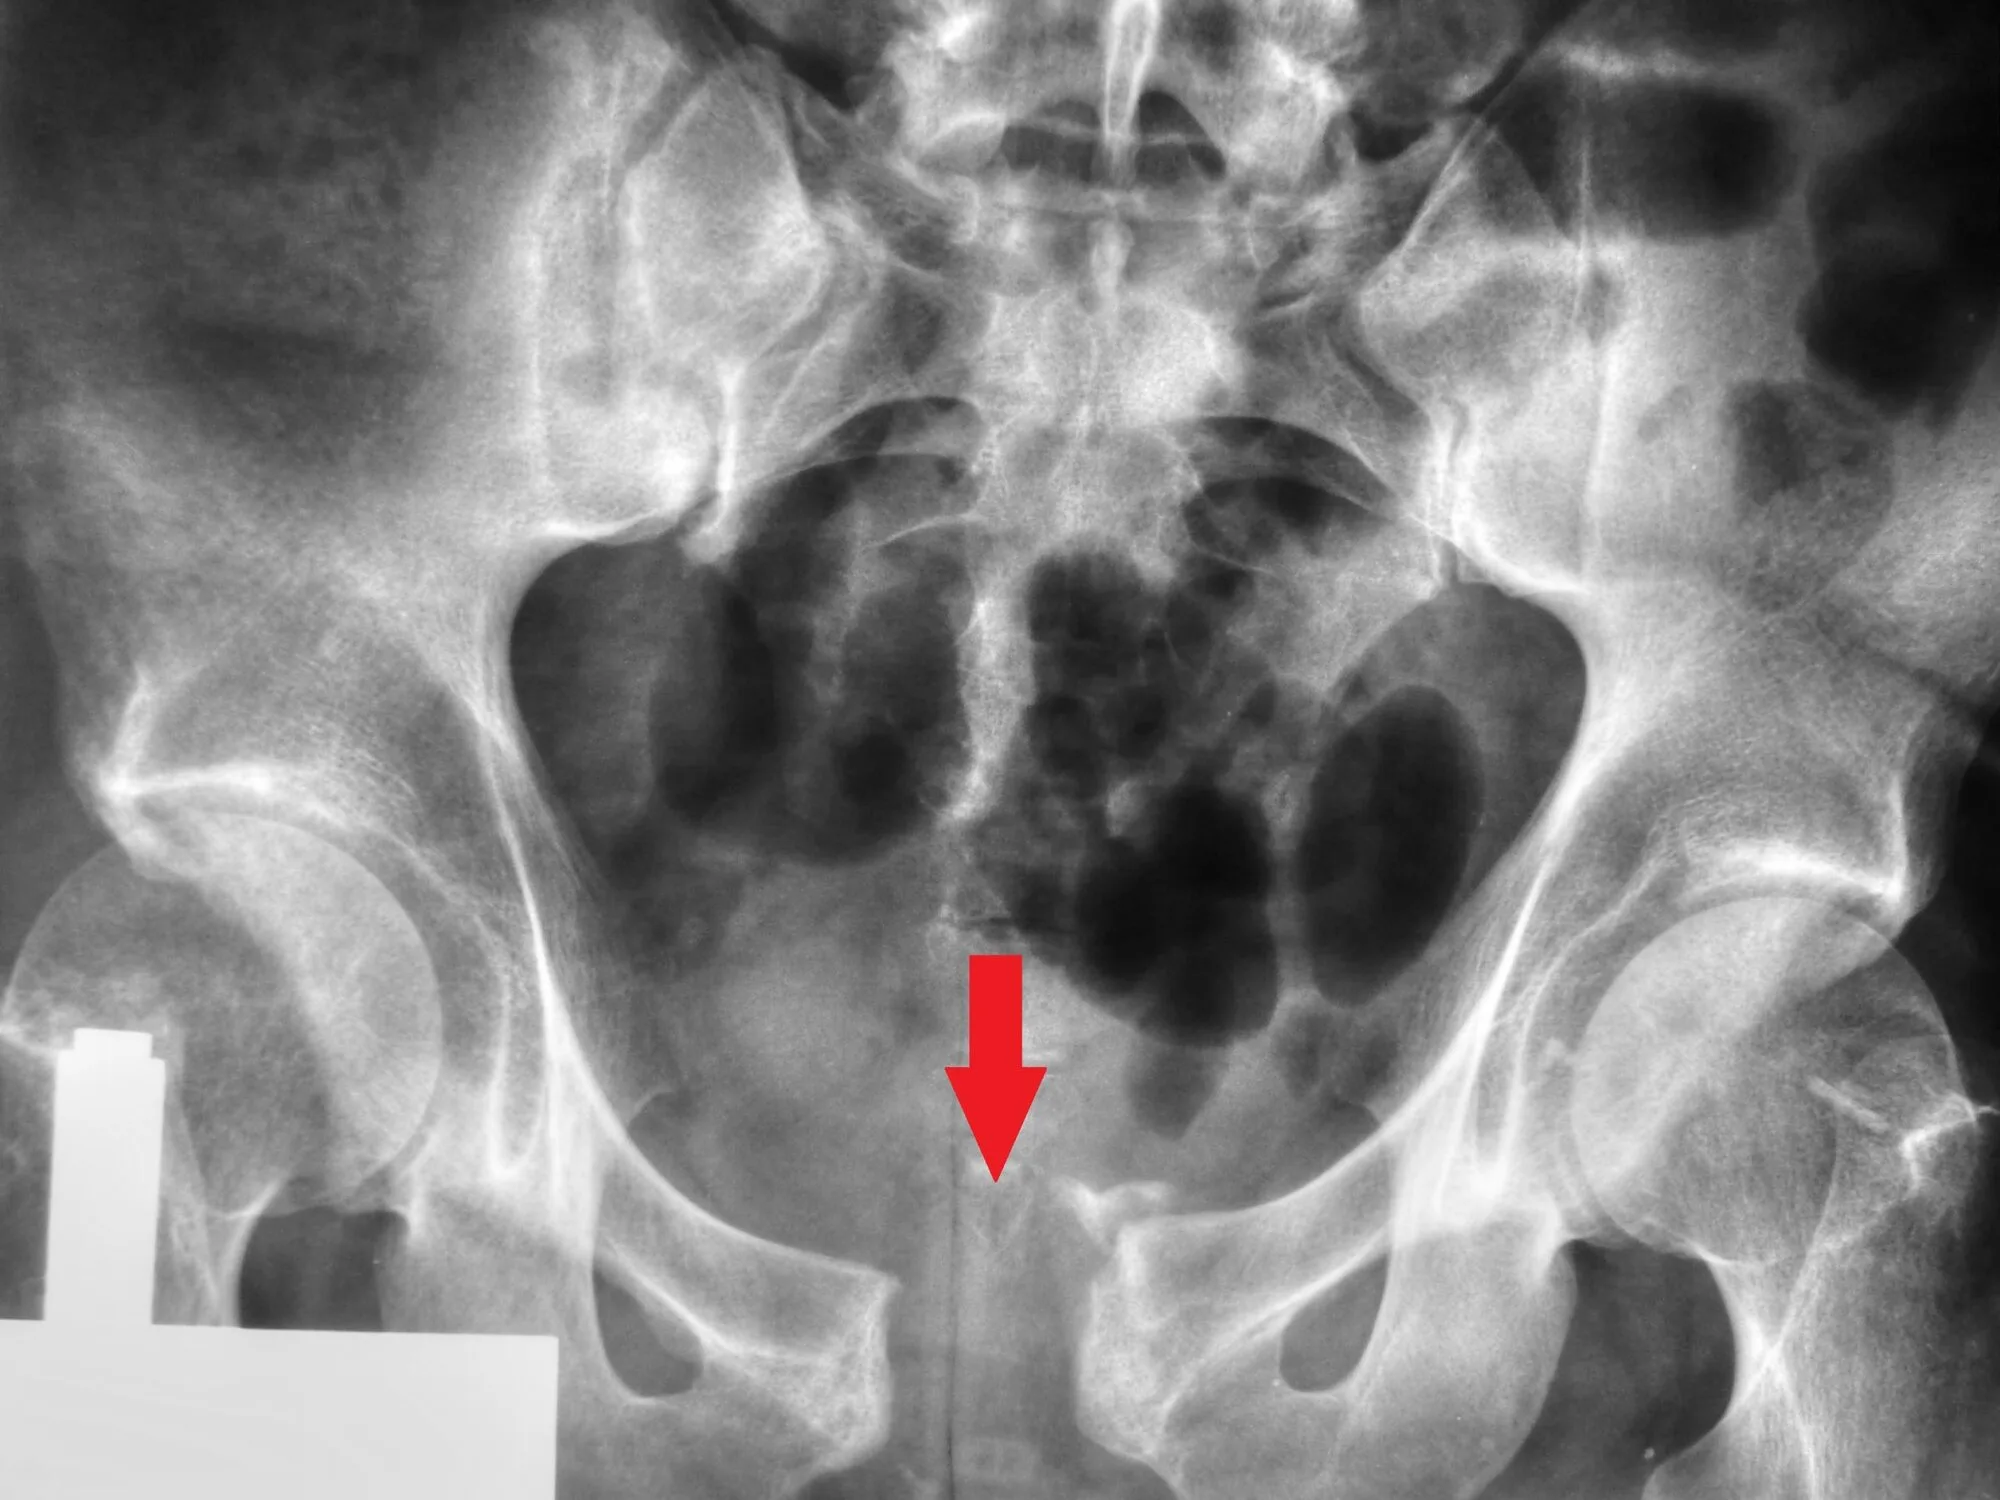

¿Qué es una fractura de pelvis?

Ocurre cuando uno o más huesos de la pelvis se rompen debido a un trauma o impacto fuerte.